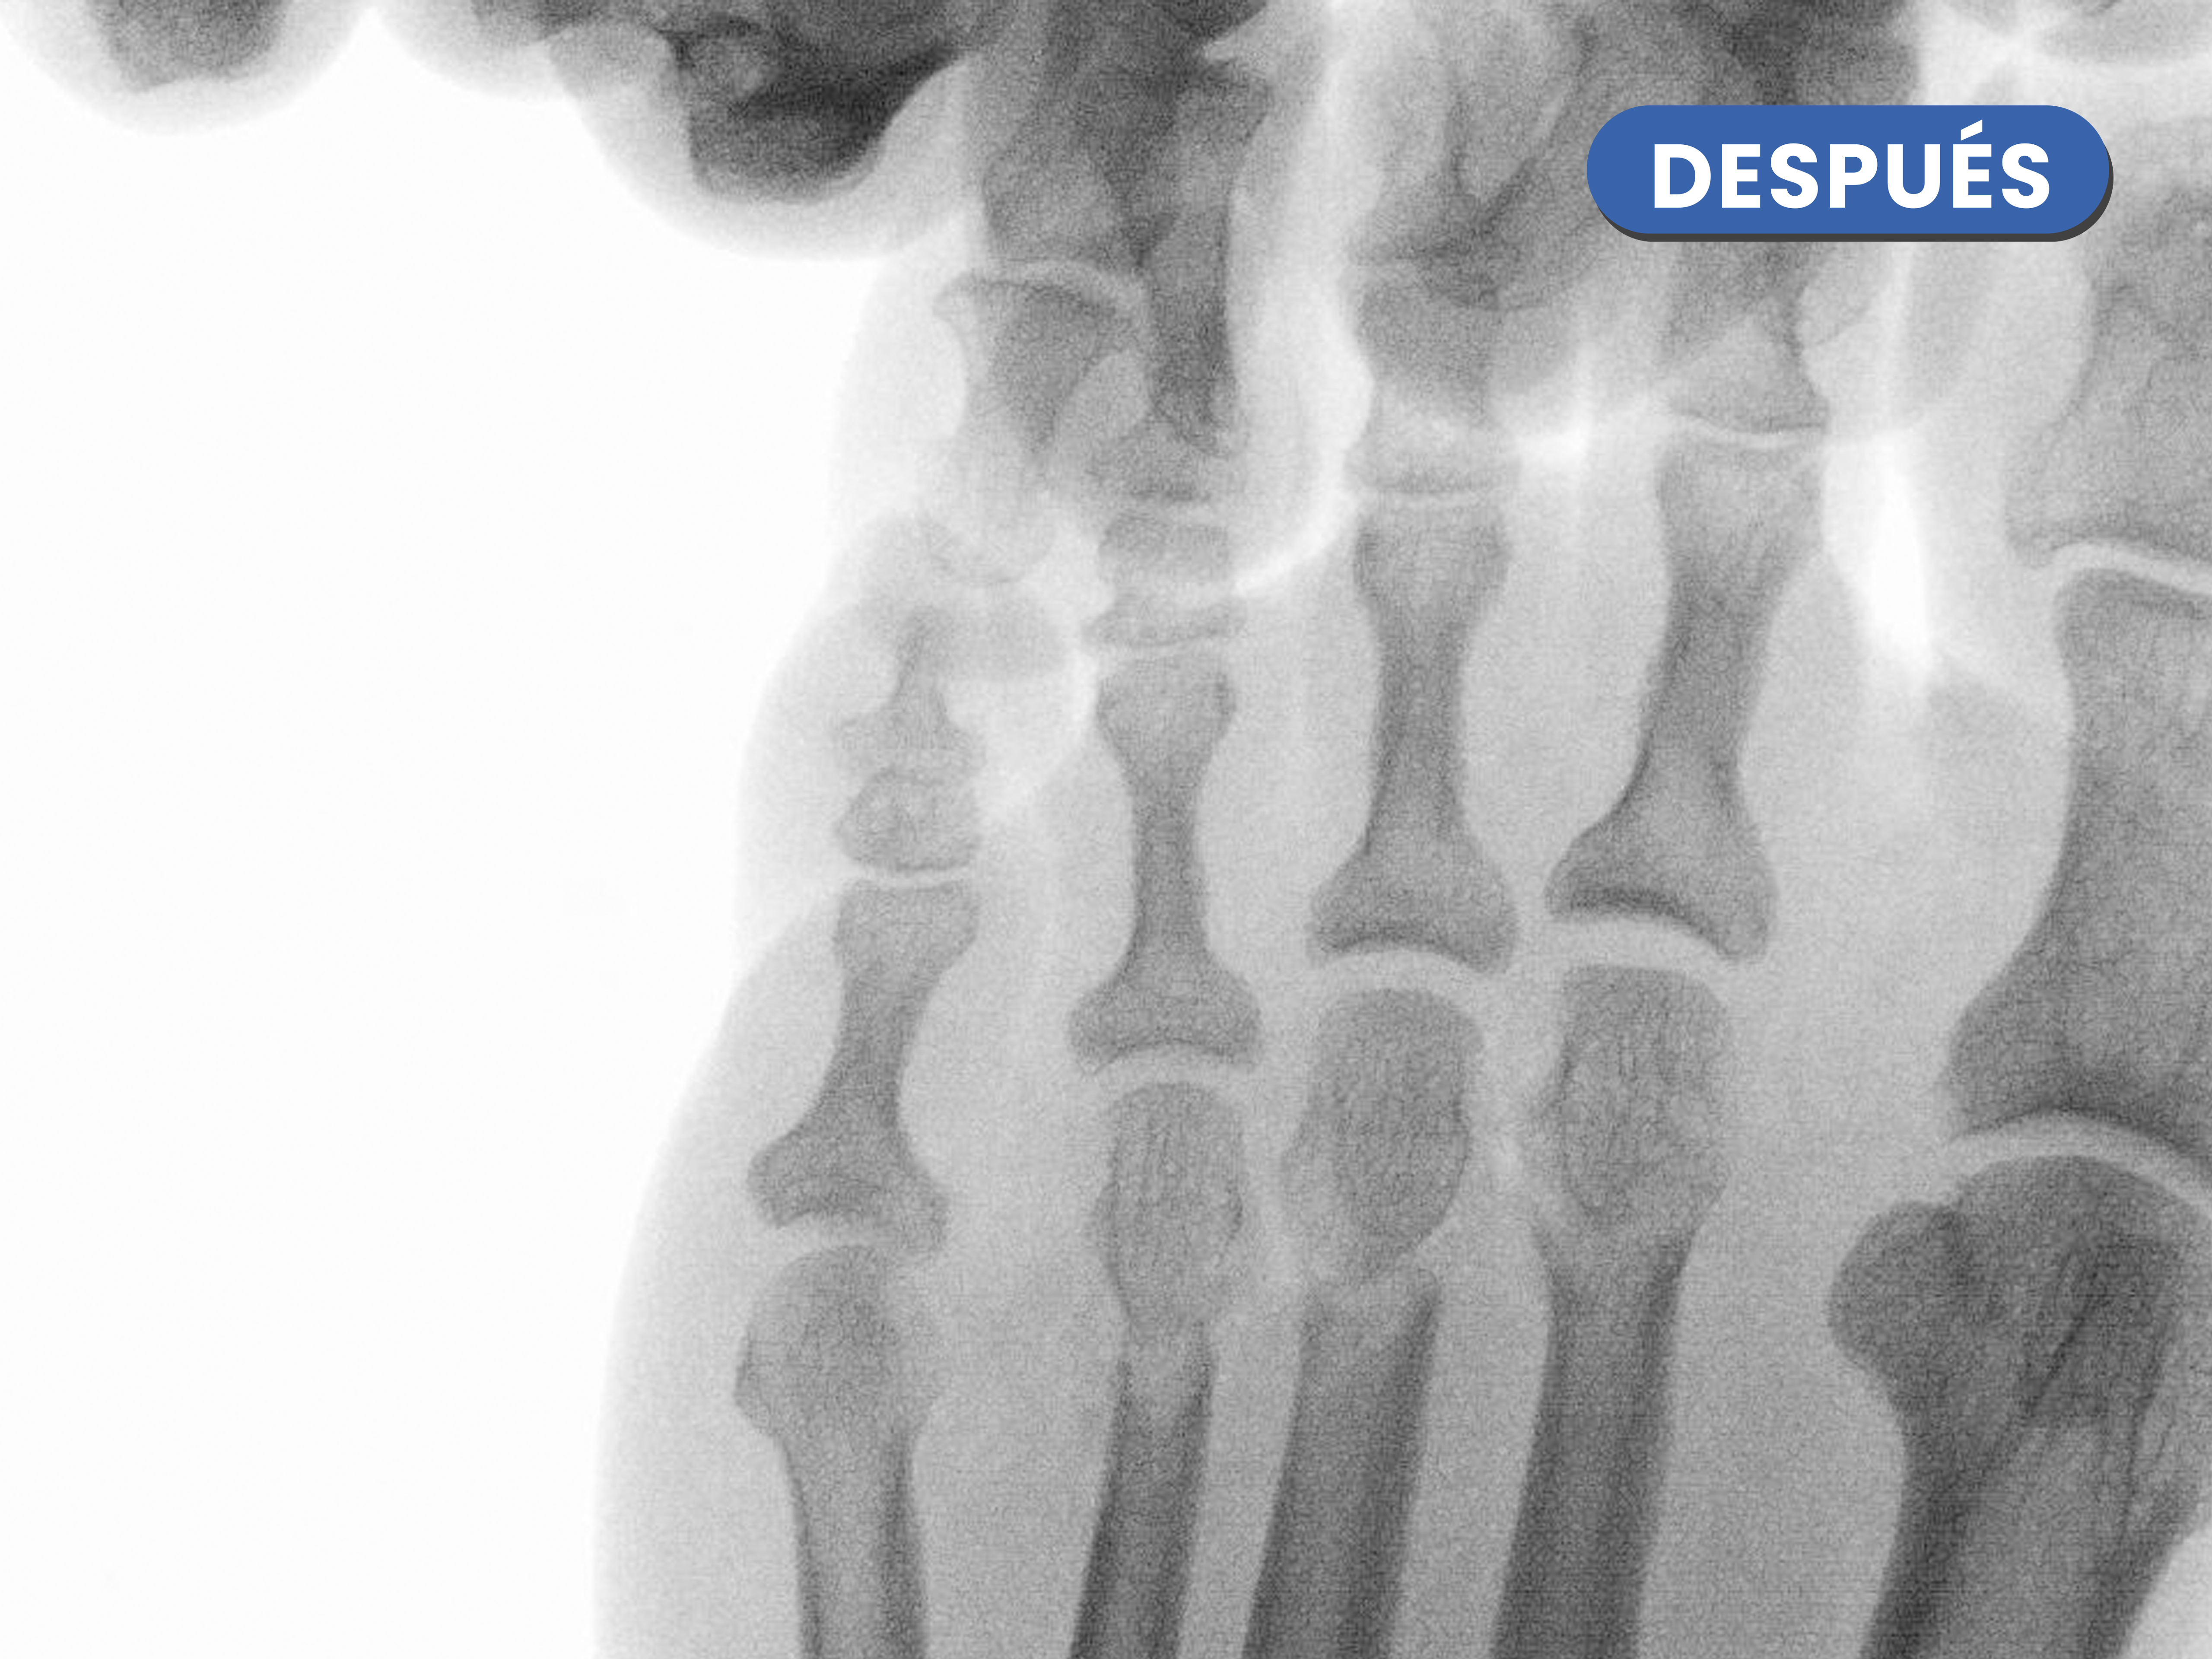

Se puede observar las osteotomía cuando realizamos operatoriamente tracción de los dedos, las osteotomías realizadas justo en el cuello del metatarsiano, se visualizan de manera completa y al caminar se produce un reajuste de la carga en la zona.

En este caso destaca la corrección metatarsofalángica tras la realización de la osteotomía metatarsal y osteotomía de la falange proximal del cuarto dedo, generandose esa línea o espacio articular entre ambos.